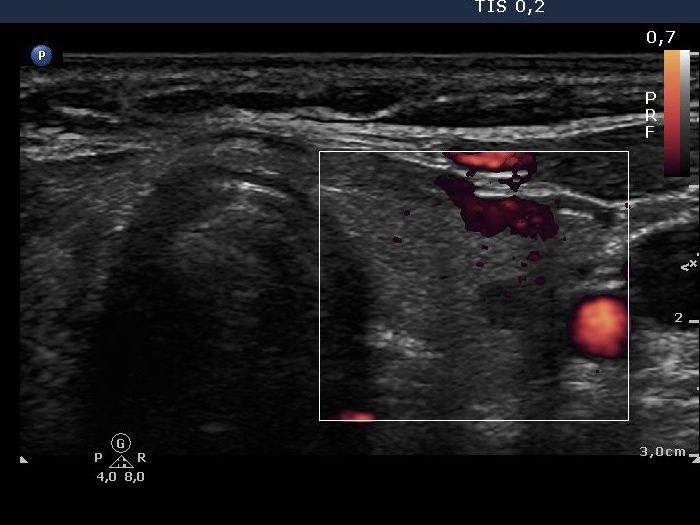

Left lobe, transverse scan, color Doppler mode. The vascularization is decreased but not absent.